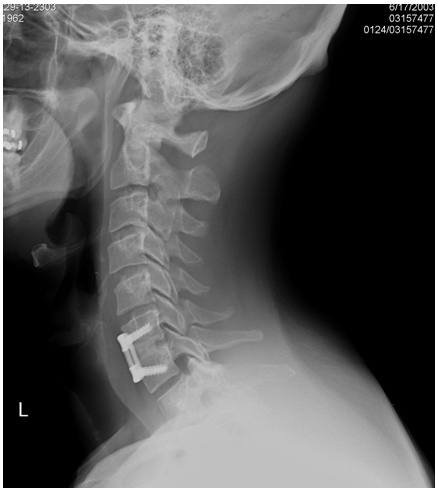

Dogmama, do you have hardware in your neck too? Maybe that's why I don't have to stay collared for 6+ weeks. Pic below, not my neck, I actually have 3 screws, this one only has 2.

Attached Thumbnails Attached Thumbnails Click image for larger version.

Name:	fusion-fig2c.jpg

Views:	199

Size:	73.1 KB

ID:	7893